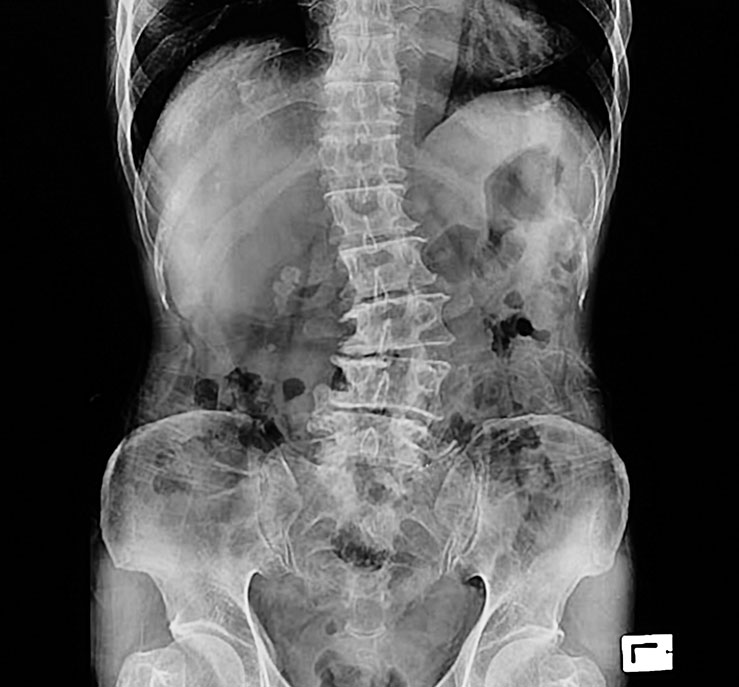

Le rôle des radiographies : voir ce qui ne fait pas nécessairement mal

Pour plusieurs, les radiographies créent un déclic.

Elles donnent enfin un sens à ce qui semblait incohérent :

Pourquoi je souffre maintenant? Pourquoi maintenant et pas avant? Pourquoi ça a “lâché” d’un coup?

Les radiographies n’expliquent pas toujours le symptôme exact du jour, mais elles montrent le terrain dans lequel vos douleurs apparaissent :

• Perte d’espace discal

• Arthrose

• Remodelage osseux

• Altération des courbures

• Calcifications

• Dégénérescences d’usure

Ces changements ne sont pas apparus en une semaine, ni en un mois.

Ils reflètent un processus installé depuis longtemps — tout comme un frigo qui fonctionne “correctement”, mais dont les composantes internes fatiguent depuis des années.